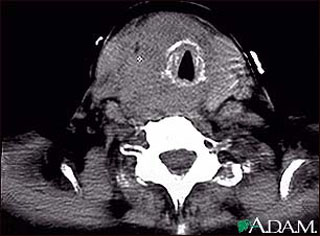

7. Thyroid Cancer

The most common thyroid cancer types are follicular and papillary which are very curable. If treated correctly, both papillary and follicular cancers have a more than 97% cure rate in young people. In the case of both papillary and follicular cancers, there is complete removal of the lobe of the thyroid where the cancer originates along with the removal of most or all of the other side.